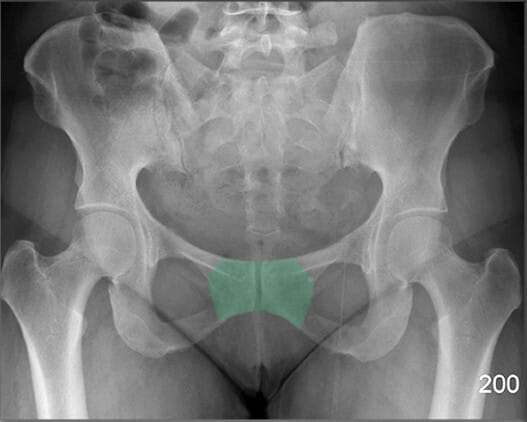

치골결합 (Pubic Symphysis)

| 치골결합 (Pubic Symphysis) |

| ✅ 치골의 정중앙에서 좌우를 연결하는 섬유연골 관절로, AP view에서 골반 중앙 하단에서 좁은 간격의 음영으로 보입니다. |

| 🔴 외상이나 분만 후 이완이나 분리(pubic diastasis)가 발생할 수 있습니다. |